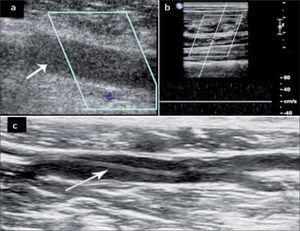

A través del modo B se puede ver directamente la presencia de un trombo o una vena no colapsable a la presión lo que indica que su lumen está ocupado (fig 8a).

Con los tres métodos de doppler, bajando al máximo el PRF y los filtros, se demuestra la falta de flujo en el vaso (Fig 8b).

Mientras más reciente es el trombo se observa más hipoecogénico con el lumen del vaso aumentado. La trombosis antigua se ve como un trombo ecogénico, retraído y con un vaso de menor calibre (fig 8).